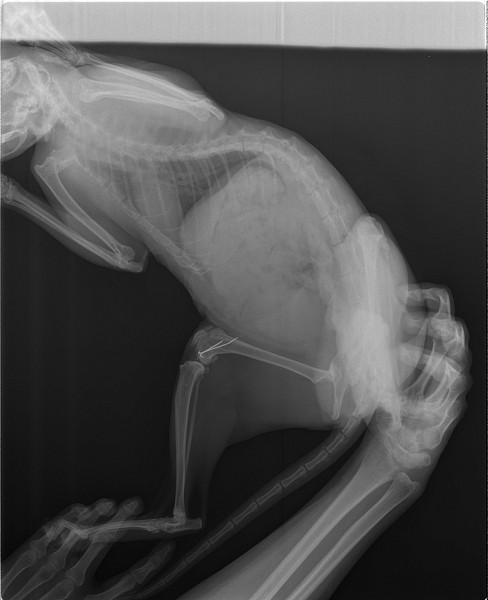

Рентген Задней Лапы Кошки: Нормы и Диагностика